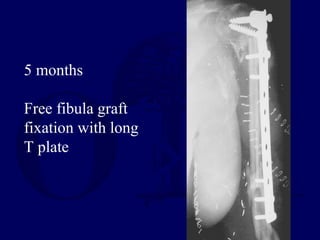

5 months

Free fibula graft

fixation with long

T plate

5 months Free fibulagraft fixation with long T plate

• #37 At 5 months post-injury, a free fibula graft was performed using a long lateral T plate for fixation.